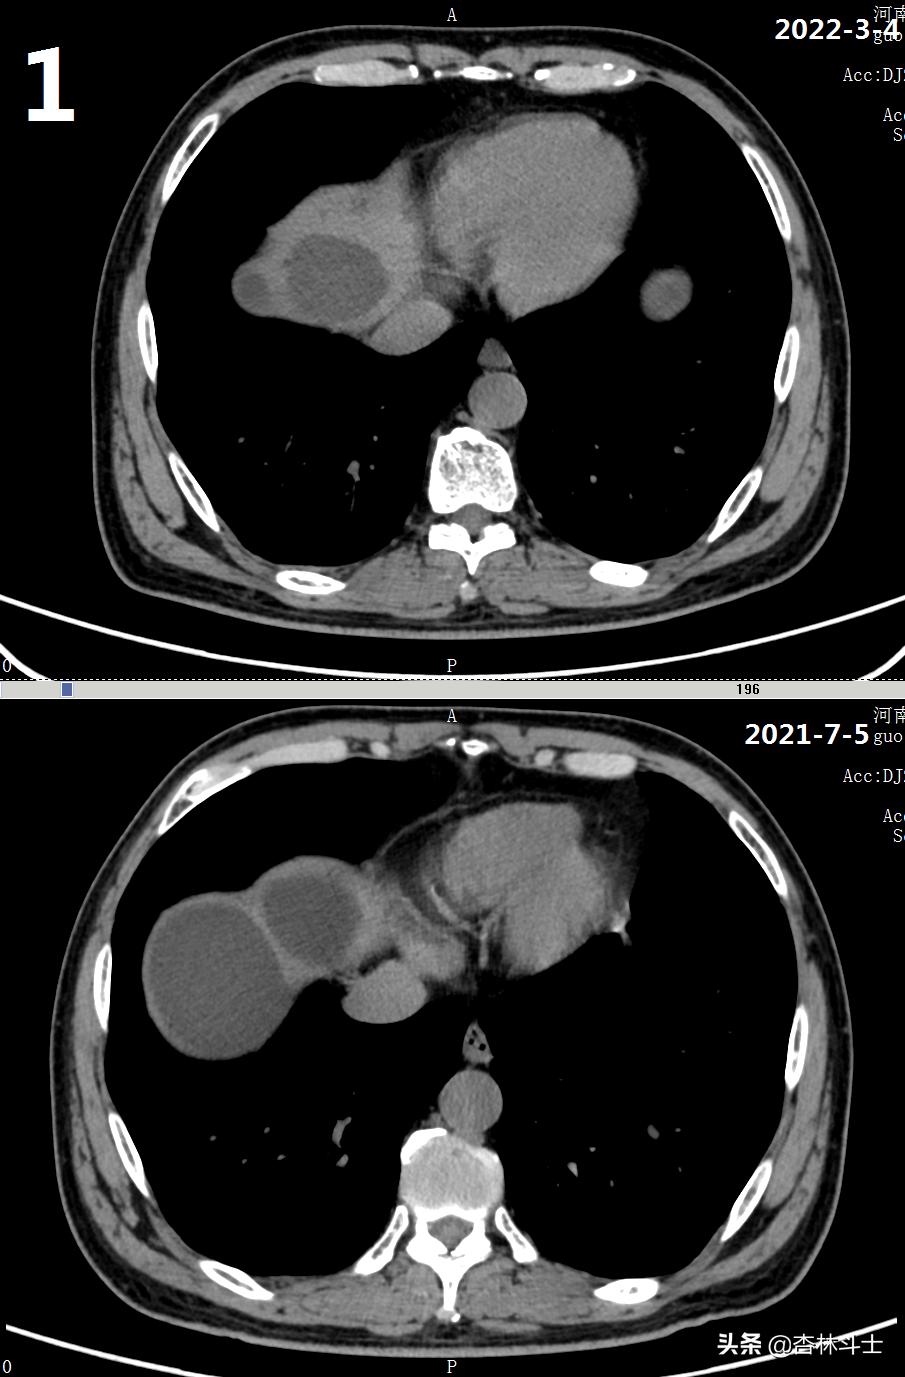

64岁退休银行职员,腹胀5年,加重2月,第二次入住我院消化内科。下图1-6为本次复查上腹部CT与2021-7-5肝囊肿经皮肝穿刺抽吸无水酒精硬化术前的对比图。

可明显看出,肝内囊肿较前减少,肝实质所占体积明显增加。